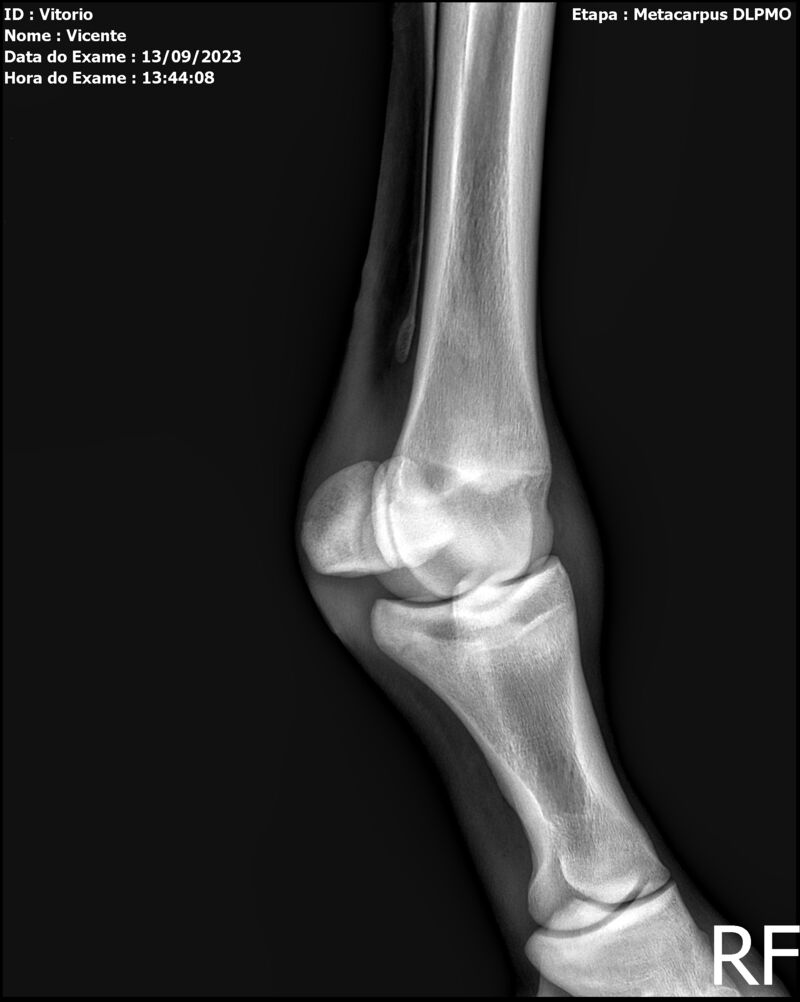

THUNDER ZC

Raça: BRASILEIRO DE HIPISMO

Sexo: MACHO - POTRO

Nascimento: 17/09/2022

Altura Aproximada: 1,54

Pel.: CASTANHO

Registro: EM AND

Vend.: VICENTE CONTE

Local : PORTO FELIZ/SP